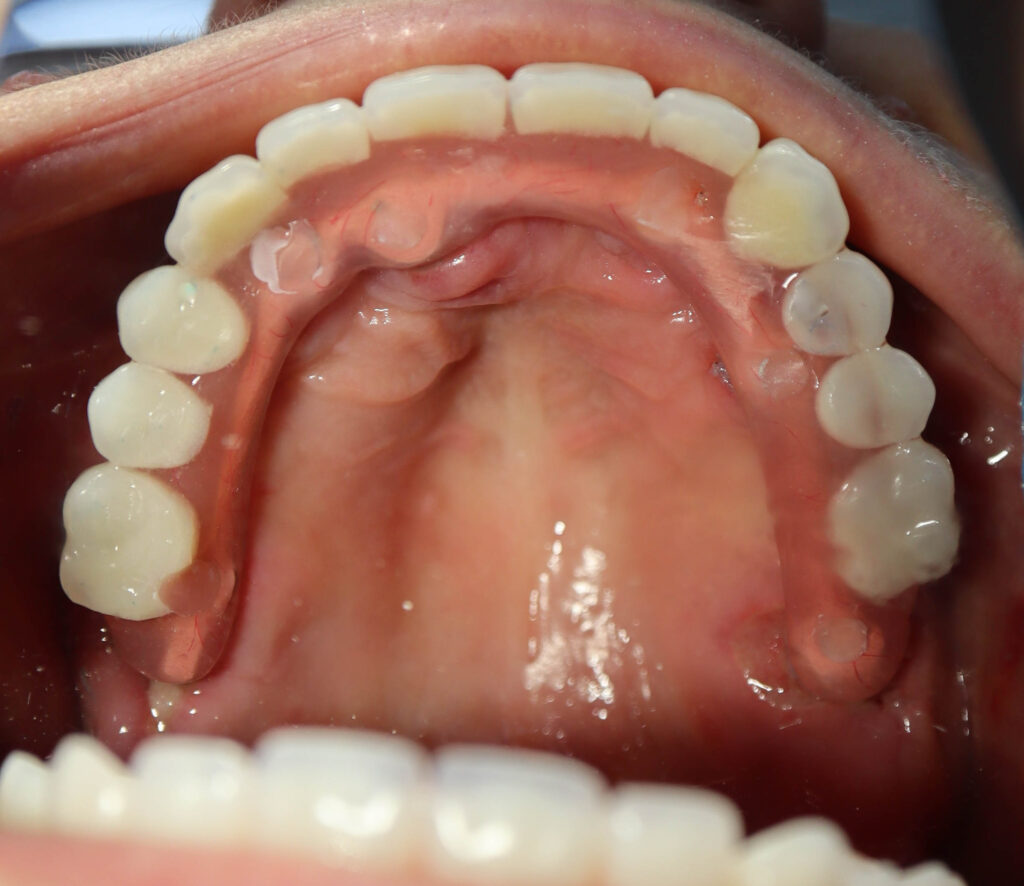

результат имплантации